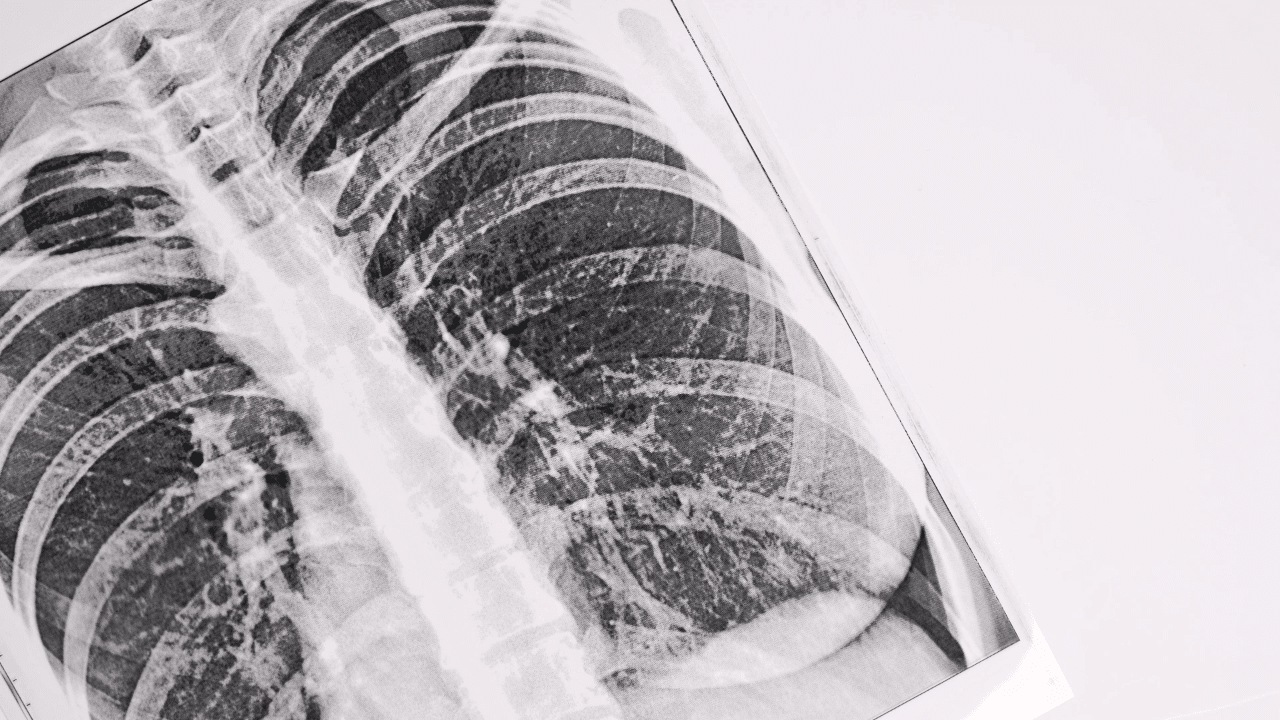

Bronchitis is a widespread respiratory condition that affects millions around the globe. It occurs when the bronchial tubes—responsible for carrying air to and from the lungs—become inflamed. This article explores the key aspects of bronchitis, from symptoms and unexpected causes to modern treatments and natural remedies like the Tiger Milk Mushroom.

Bronchitis falls into two main categories: acute and chronic.

Acute bronchitis is usually triggered by viral infections and lasts for a few weeks.

Chronic bronchitis, a form of chronic obstructive pulmonary disease (COPD), involves persistent inflammation and mucus production over months or years.